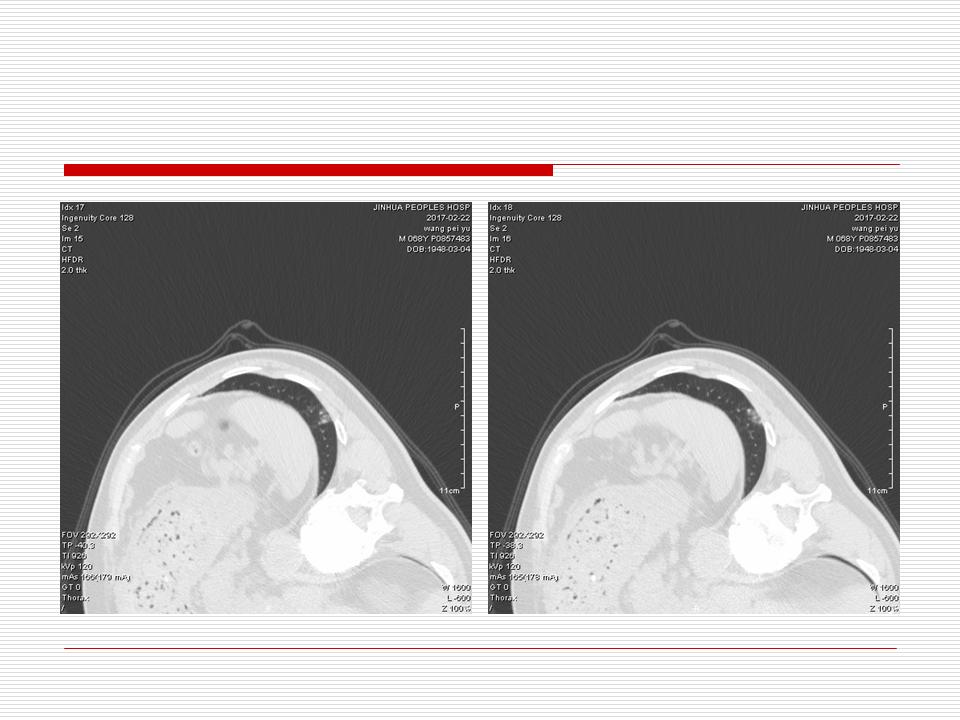

肺部阴影永恒且最重需要鉴别的是:到底是炎症还是肿瘤?但临床的病例中的影像表现难以界定或有些肿瘤特征,同时又有些炎症特点是非常常见的情况。作为临床医生我们怎么去总结分析,并找到之所以是炎症或之所以是肿瘤的细微差别或特点非常重要,也非常有用。2019.12.7浙江省2019年胸心外科学学术年会在宁波召开时,我的临床病例分析与经验总结<那些像肺癌的炎症与像炎症的肺癌>获得在大会交流的机会,以下为该PPT的内容,与你分享,希望对同道有益,有借鉴与启迪。若有探讨与进一不完善的建议,欢迎文末留言讨论: